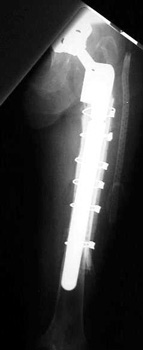

Long stem revised femoral component with periprosthetic fracture